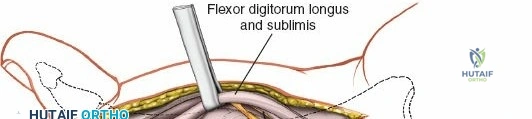

A thorough understanding of the intricate anatomy and biomechanics of the flexor tendon system is non-negotiable for any surgeon employing a volar approach. The digital flexor system comprises the Flexor Digitorum Superficialis (FDS) and Flexor Digitorum Profundus (FDP) tendons. The FDP tendon originates from the ulna and interosseous membrane, inserting onto the volar base of the distal phalanx, primarily responsible for DIP joint flexion. The FDS tendon originates from the medial epicondyle, ulna, and radius, typically bifurcating around the FDP in the region of the proximal phalanx (Camper's chiasm) before inserting onto the middle phalanx, primarily flexing the PIP joint.

Within the fibro-osseous tunnel, these tendons are enveloped by a synovial sheath that facilitates smooth gliding and nutrition. The integrity of the pulley system, composed of annular (A) and cruciate (C) ligaments, is critical for preventing tendon bowstringing and maintaining efficient mechanical advantage. Typically, five annular pulleys (A1-A5) and three cruciate pulleys (C1-C3) are described in each finger. The A1 pulley is at the metacarpophalangeal (MCP) joint level, A2 at the proximal phalanx, A3 at the proximal interphalangeal (PIP) joint, A4 at the middle phalanx, and A5 at the distal interphalangeal (DIP) joint. The A2 and A4 pulleys are considered the most critical for preventing significant bowstringing.

Once the subcutaneous tissue and neurovascular bundles are retracted, the fibrous flexor sheath is visible. This appears as a glistening white, tough structure enveloping the flexor tendons.

The sheath is incised longitudinally. The specific pulleys that need to be released depend on the pathology and zone of injury.

- A1 Pulley Release: For distal palmar or MCP joint access (e.g., trigger finger release, A1 pulley excision for tumor). The A1 pulley can be completely incised longitudinally from proximal to distal without significant risk of bowstringing, as the A2 pulley is the primary stabilizer at the proximal phalanx base.

- Digital Pulleys (A2-A5, C1-C3):

- For flexor tendon repair, typically the A2 and A4 pulleys must be preserved to prevent bowstringing, which significantly impairs mechanical efficiency.

- The A1, A3, and A5 pulleys, and the cruciate pulleys (C1, C2, C3), can be incised longitudinally or partially vented to expose the tendons and allow for repair.

- When accessing Zone II (no-man's land), the incision usually involves opening the A1, A3, and C1/C2/C3 pulleys, carefully preserving the A2 and A4 pulleys.

- In cases of extensive trauma or adhesions, careful piecemeal division of pulleys may be necessary to gain adequate exposure for repair or tenolysis, with a plan for potential pulley reconstruction if significant bowstringing is anticipated.

Once the flexor sheath is opened, the FDS and FDP tendons are exposed.